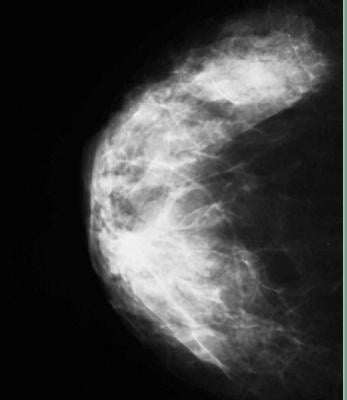

The accurate measurement of mammographic density offers the potential to improve breast cancer risk prediction and to tailor screening protocols according to risk, according to a study published in Breast Cancer Research (16:439 doi:10.1186/s13058-014-0439-1). The article, “Digital mammographic density and breast cancer risk: a case-control study of six alternative density assessment methods,” demonstrates a strong connection between breast density and breast cancer risk.

The study details the results of a comprehensive comparison of available mammographic density measurement tools and their ability to predict breast cancer risk. The performance of three area-based approaches (BI-RADS, the semi-automated Cumulus, and the fully-automated ImageJ-based approach) and three fully-automated volumetric methods (VolparaDensity from Volpara Solutions, Quantra from Hologic, and single X-ray absorptiometry (SXA)) were assessed in 3,168 digital mammography images. This included cancer cases diagnosed at Royal Marsden Hospital in London and normal mammograms from the England and Wales national mammographic screening program.

“Mammographic density is one of the strongest risk factors for breast cancer and is increasingly being used to tailor preventive and screening strategies to a woman’s risk. It is also a major determinant of the sensitivity of mammographic screening and, by extension, the detection of interval cancers. Consequently, in many US states, it is now mandatory to inform screening-attendees of their density,” said Isabel dos-Santos-Silva, M.D., professor of epidemiology at the London School of Hygiene and Tropical Medicine, UK. “The results show that the mammographic density measurements yielded by automated volumetric measurements are as good predictors of breast cancer risk as those generated by well-established, but more labour-intensive methods such as Cumulus.”

All six density assessment methods showed that percent density was inversely associated with age and body mass index (BMI), and certain reproductive factors. While all of the methods produced positive associations of density with risk, the association was highest for Volpara and Cumulus. Volpara and Cumulus were also the only tools that produced breast density measures for all images in the study, with other methods failing to produce readings for up to 11% of the participants. Women with the highest density had 8.26 times the risk of those with the lowest breast density as measured by Volpara on this dataset (the 95% confidence range was 4.28-15.96). The results also suggest that Volpara is better at identifying women at low risk than the other methods.